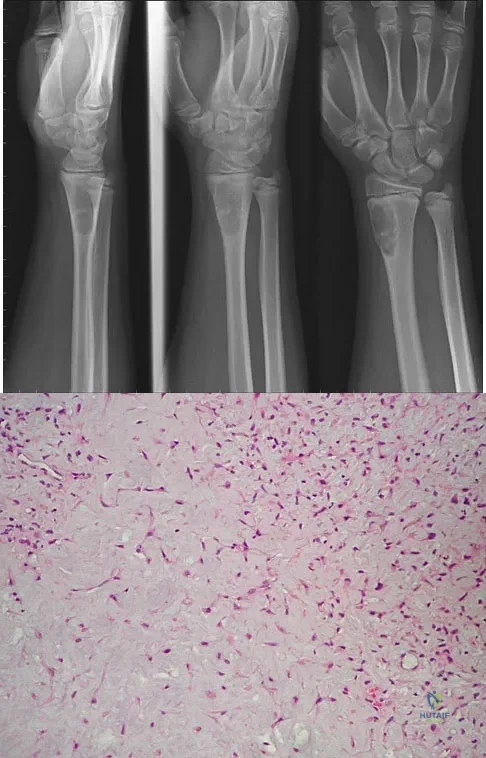

A 14-year-old boy reports progressive right wrist pain. Radiographs are shown in Figure 3a, and a photomicrograph is shown in Figure 3b. What is the most likely diagnosis?

A 16-year-old girl has had anterior leg pain and a mass for the past 8 months. Figures 2a and 2b show a radiograph and an H & E histologic specimen. Which of the following disorders is believed to be a precursor of this lesion?

Figures 19a and 19b show the AP and lateral radiographs of an 18-year-old man who has had knee pain for 3 months. Figure 19c shows a histopathologic photomicrograph of the biopsy specimen. Which of the following factors is most likely to affect his survival?